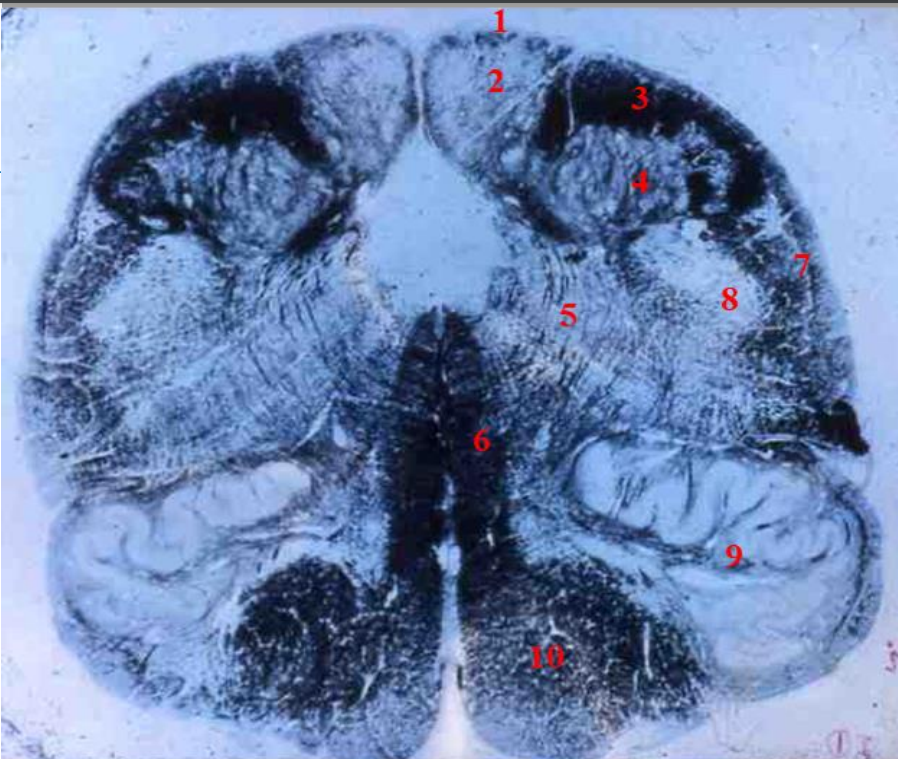

3

4

5

Perfectly

6

Q

1

A

fasciculus gracilis

How well did you know this?

9

parts of the thalamus